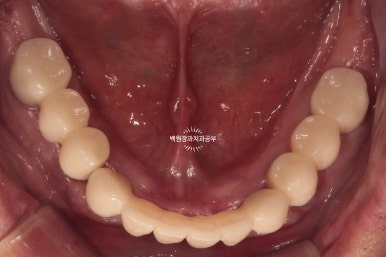

최종 보철물.. 드디어 제작이 되었습니다.

사실 정말 정말 감동적인 순간입니다... 우리 환자분께서 이 날만을 얼마나 기다리셨을까요.....

전체 임플란트를 완성하는데 전체 치료기간은 약 8개월 정도 걸렸습니다. 상당히 빨리 졸업하신 편이에요!

정면에서 보시면 임시 치아와 다르게 훨씬 깊이감 있는 색상으로 제작되어 자연스럽고, 완성도 있는 형태를 확인하실 수 있습니다.

그리고 치과용 파노라마로 확인해보시면, 정확한 위치에 정확한 보철물이 제작되어 상당히 조화로운 결과를 확인하실 수 있으실거에요! 치과의사로 살면서 가장 기쁘고 감동적인 순간 중 하나입니다.

정말 너무너무 보람찹니다 :) ㅎㅎ 환자분께서도 굉장히 만족해하셨어요!

금호동 전체 임플란트 전문 치과 대표 원장인 저와 보철과 원장님이 함께 최선을 다해 작업하였습니다.!!